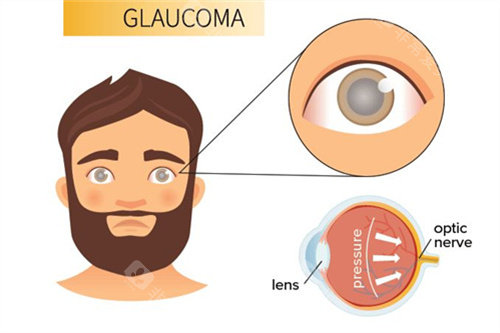

青光眼正规则专注于青光眼的早期诊断和个性化治疗,通过较高的检查设备和治疗手段,有效控制眼压,保护患者的视力。